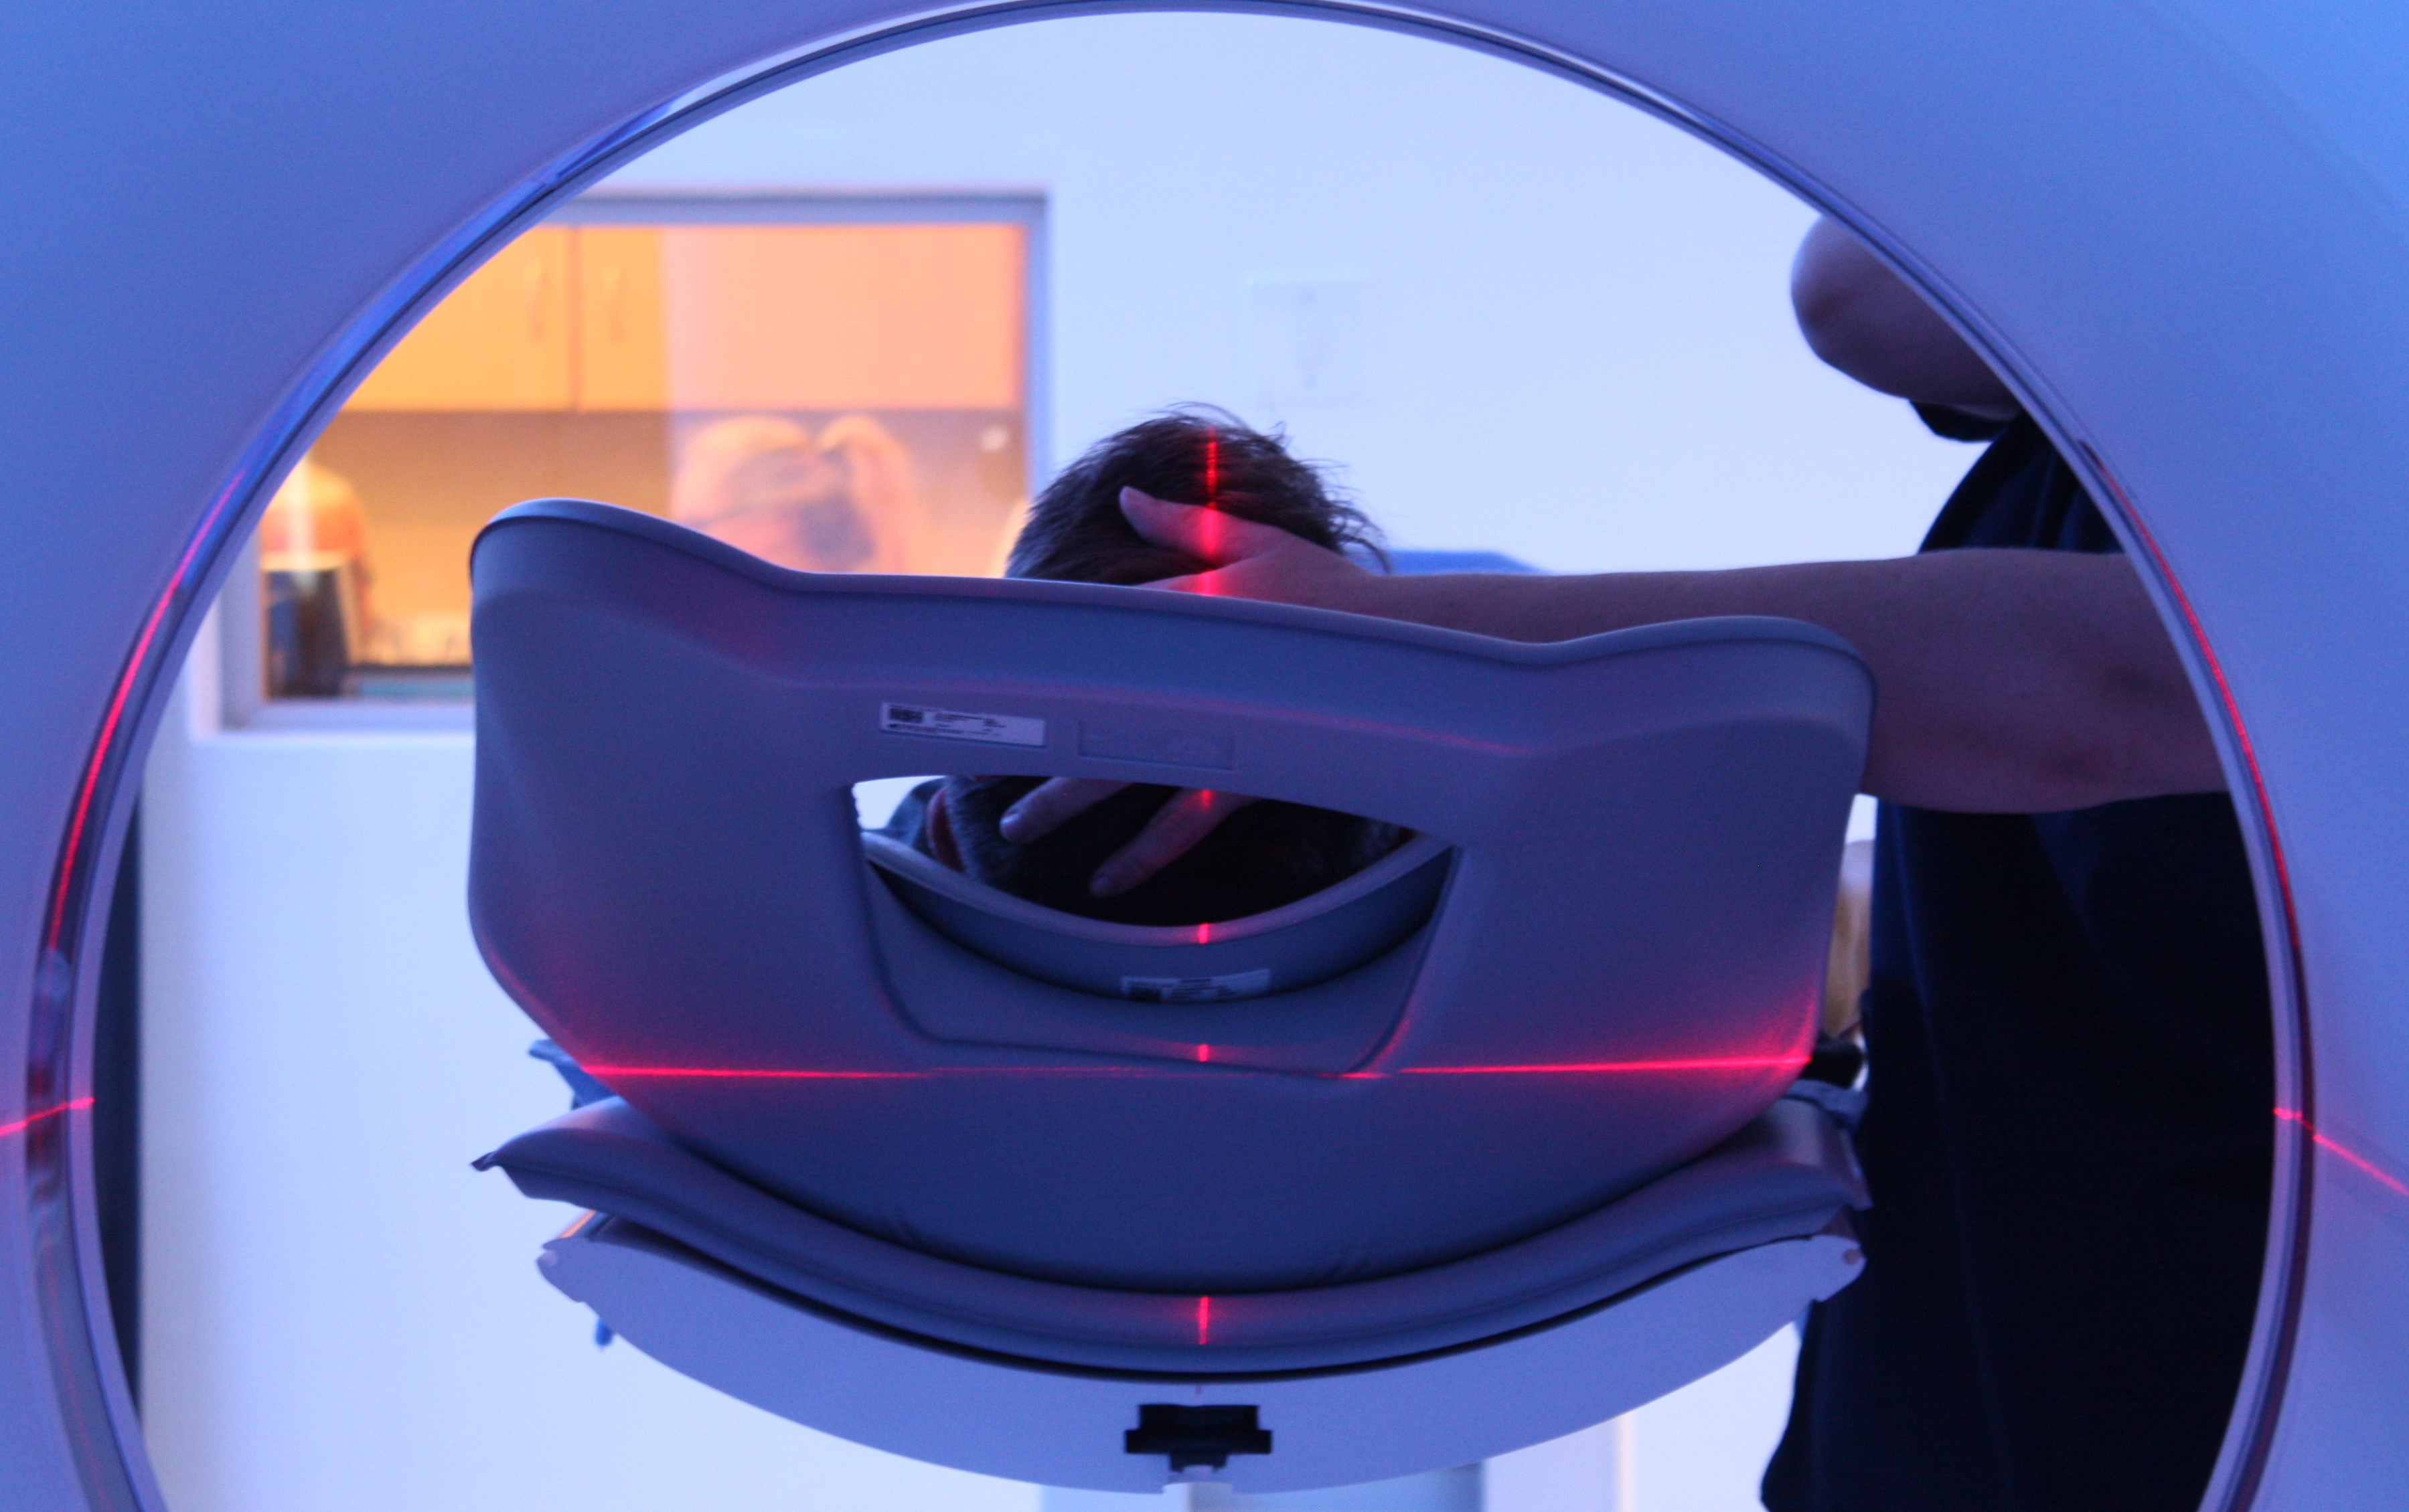

This advanced nuclear imaging technique combines positron emission tomography (PET) and computed tomography (CT) into one machine. A PET/CT scan reveals information about both the structure and function of cells and tissues in the body during a single imaging session.

Read MoreThe last few years have seen unprecedented advances in medical imaging techniques, allowing doctors an extraordinary view into the human body and the opportunity to fine-tune treatment. PET-CT is well established internationally as the ‘Gold Standard’ for the assessment of the extent of cancer spread in the body as well as the assessment of cancer treatment.